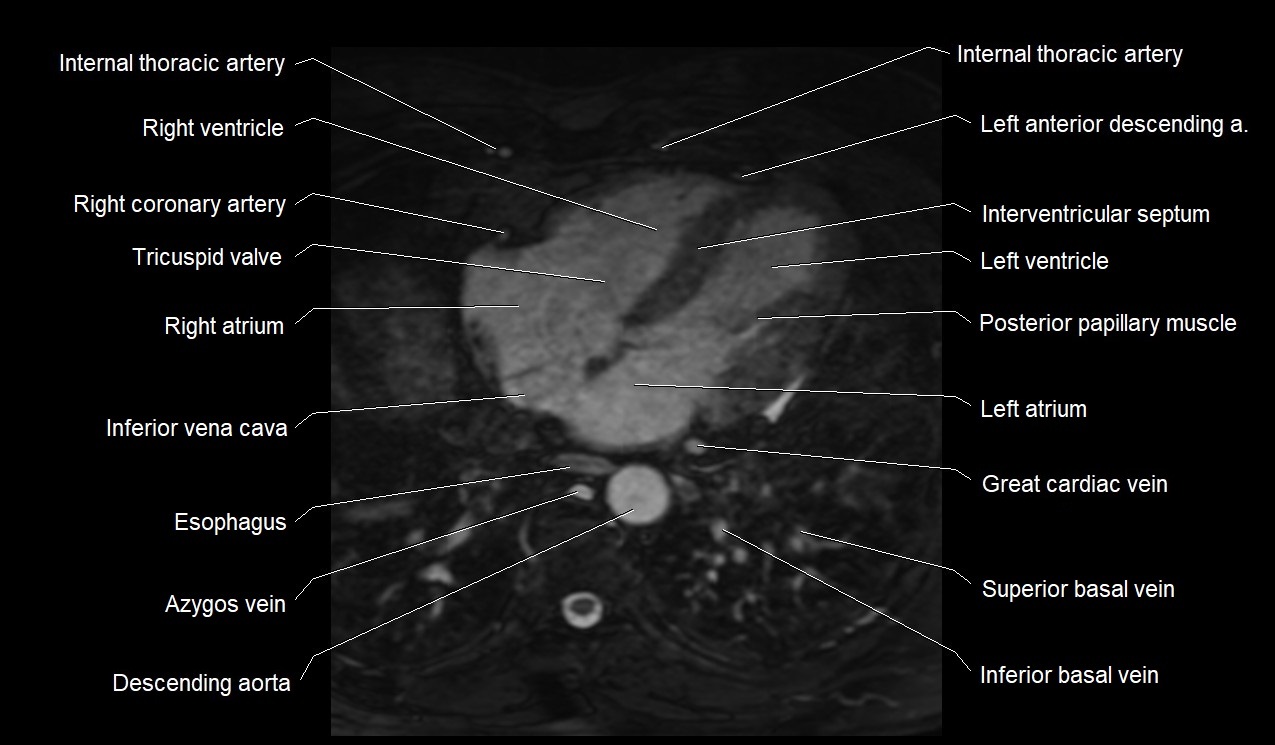

MRI image